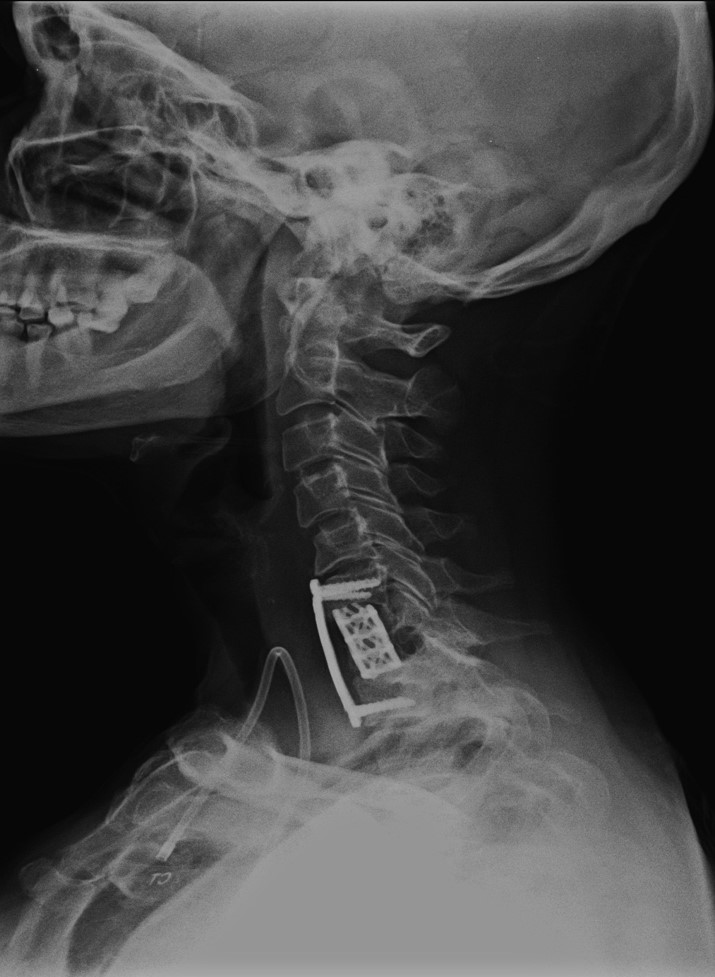

• C7 metastatik karsinoma

• 22.11.2012 servikal korpektomi yapıldı.

Ameliyat Sonrası